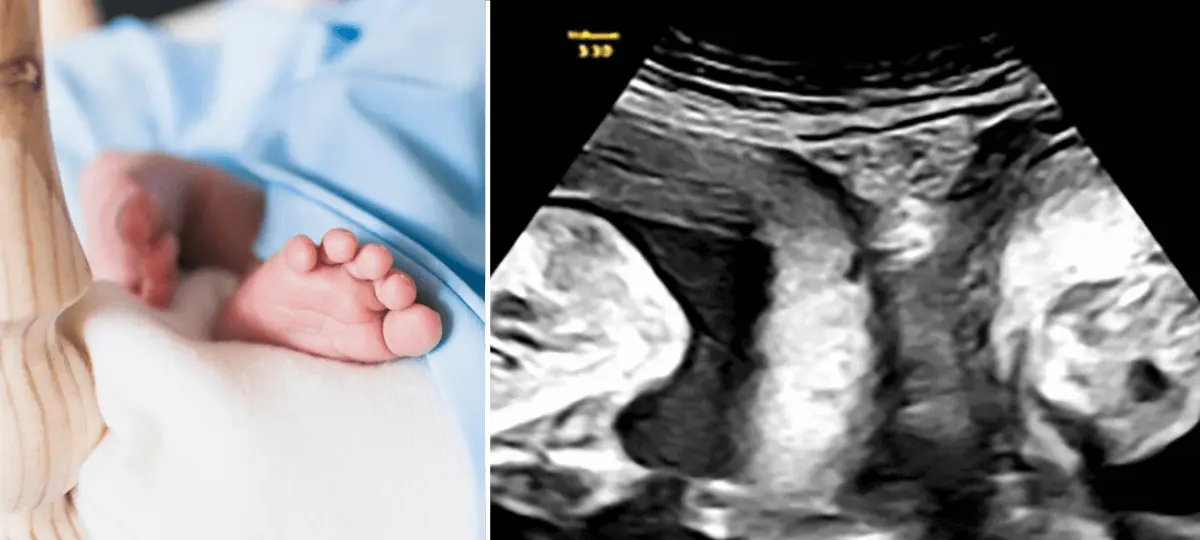

Podľa tohto vyjadrenia sa deti narodili žene s dvoma krčkami maternice a dvoma maternicami. Ide o stav zvaný uterus didelphys – čiže dvojitá maternica. Objavuje sa veľmi výnimočne, u menej ako jednej ženy z dvoch tisíc. A aby došlo u takej ženy k súčasnému oplodneniu dvoch vajíčok, je ešte oveľa menej pravdepodobné.

V januári tohto roku sa jej to ale podarilo. A ultrazvuk ukázal, že rovno dvakrát; teda že nečaká len jedno dieťa, ale dvojčatá – v každej maternici jedno. Pôrod nebol ľahký, nemocnica k nemu zvolala špeciálny tím. Ale dopadol dobre. Podľa zdravotníckeho zariadenia má chlapec 3,7 kilogramu a dievča 3,11 kilogramu.